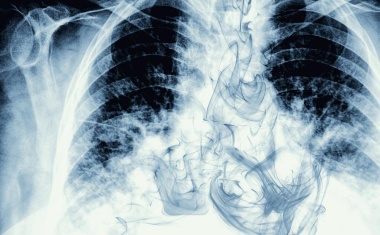

Lungenkrebs: Krankenhaus Nordwest erstes zertifiziertes Screeningzentrum in Hessen

Das Krankenhaus Nordwest erweitert mit einem Lungenkrebsscreening sein Präventionsangebot im Bereich Onkologie. Als erste zertifizierte Klinik in der Region werden hier ab sofort diese Früherkennungsuntersuchungen für Risikopatienten angeboten.